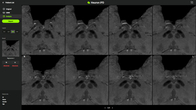

휴런, 파킨슨병 솔루션 ‘휴런 IPD’ 싱가포르 인허가 획득

- 2025-02-13 10:20

- 노영희 기자